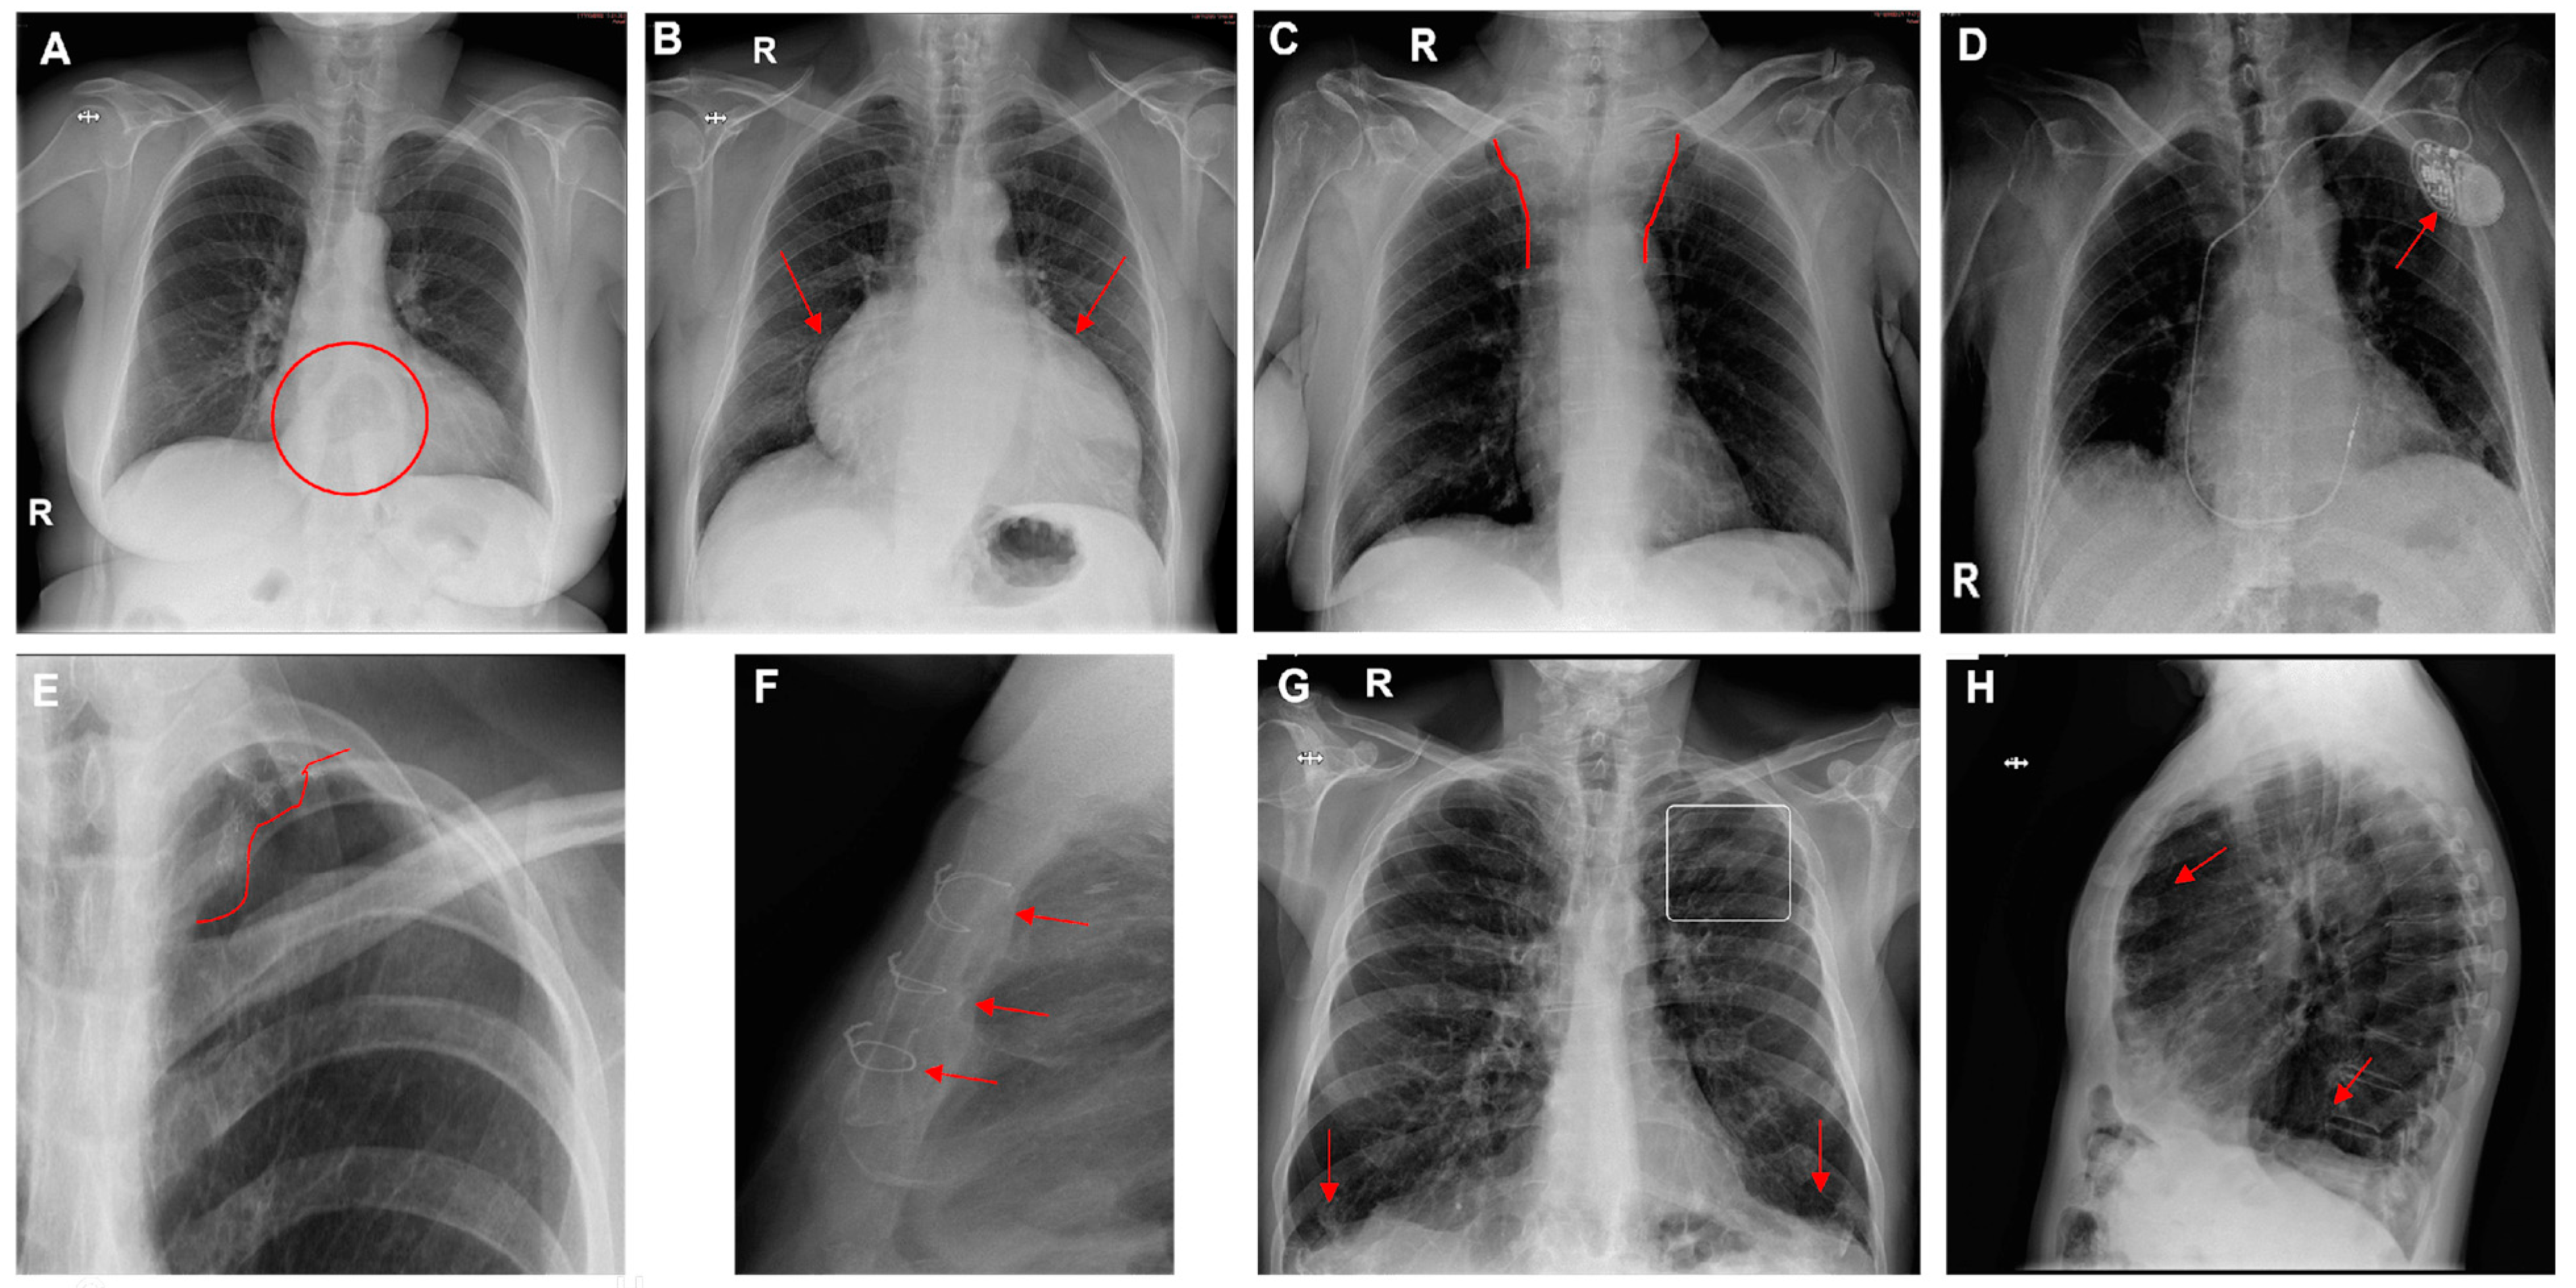

The prevalence of other variables included 16% for mediastinal abnormalities (cardiomegaly, hiatal hernia, widening of the superior mediastinum), 20% for surgical material (staples, metal valves, stents), and 20% for other pulmonary findings (pulmonary hyperinflation). Cardiomegaly was the most frequent finding (80%). Hyperinflation was found in only 7% (Figure 5 and Figure 6).

Figure 6.

Chest radiographs with additional findings highlighted by red circles, arrows, or lines. (A) Hiatal hernia, (B) cardiomegaly, (C) widening of the superior mediastinum, (D) heart pacemaker, (E) pulmonary surgical material, (F) sternal surgical material, (G,H) pulmonary hyperinflation (G—flattening of the diaphragms and enlarged retrosternal space; H—enlarged retrocardiac spaces).